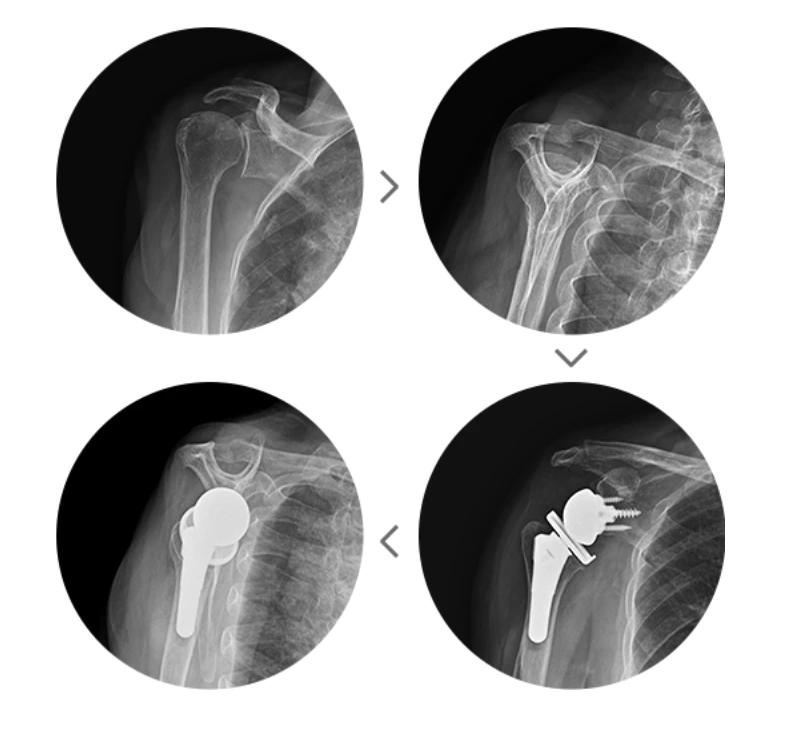

역행성 인공관절 치환술

어깨회전근의 파열이 광범위하게 진행되어 가성마비까지 발생한 상황에 선택되는 수술로 봉합수술이 아니라 견갑골과 상완골에 인공관절을 삽입해 인위적으로 관절의 중심을 이동시켜 어깨근육인 삼각근이 어깨힘줄을 대신해 팔을 들어 올리도록 해주는 수술이랍니다.

역행성인공관절치환술.PNG